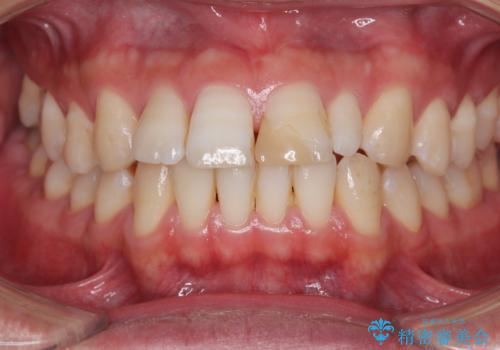

前歯の単独歯の補綴治療であったので、オーダーメイドタイプをおすすめしましたが、今回は既製タイプにて製作を進めました。

既製タイプでしたが、違和感のない仕上がりとなりました。